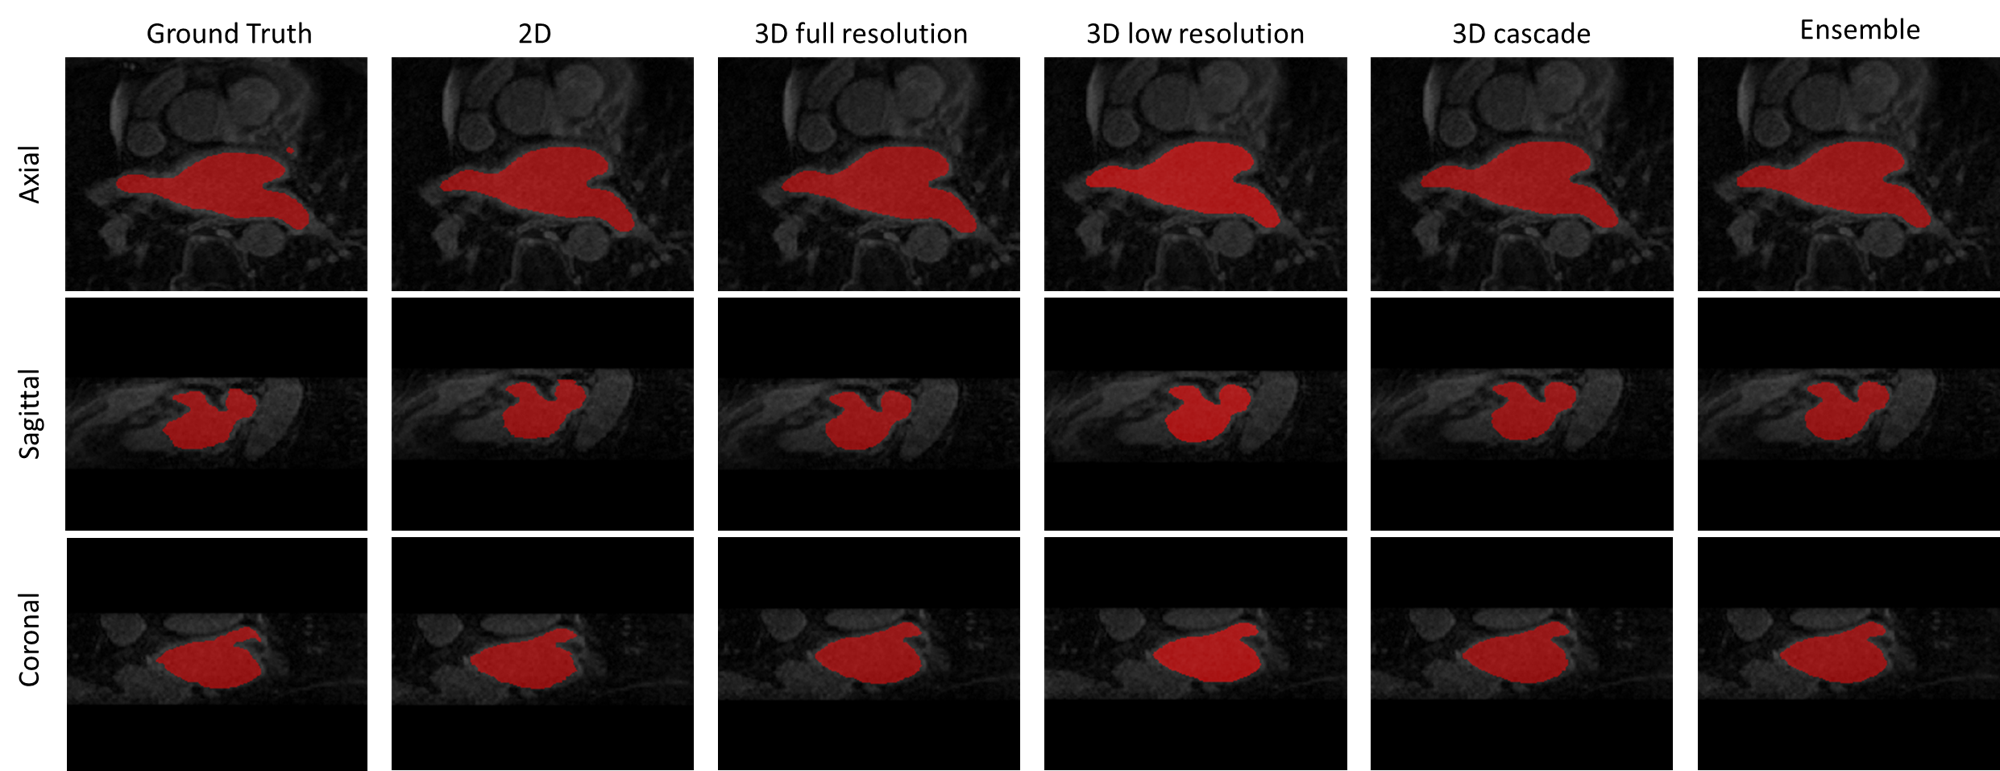

Figure 3: Comparison of ground truth and predictions from different nnU-Net Versions (2D, 3D Full Resolution, 3D Low Resolution, 3D Cascade, and Ensemble) in three anatomical views: Axial, Sagittal, and Coronal for the LASC dataset. The cavity area is highlighted in Red. Visualized using ITK-SNAP software.

For the LASC dataset, the ensemble model achieves the highest performance (Table 6). According to Table 7, nnU-Net demonstrates competitive performance with other methods, with only Singh et al. (2023a) surpassing nnU-Net by 0.1%. Interestingly, even the nnU-Net (2D) model shows competitive performance compared to the latest models (Xu et al., 2024). nnU-Net is able to surpass the novel method even without additional configurations. We assess the qualitative performance of the nnU-Nets using ITK-SNAP software (Yushkevich et al., 2016) as shown in Figure 3 for axial, sagittal and coronal views.